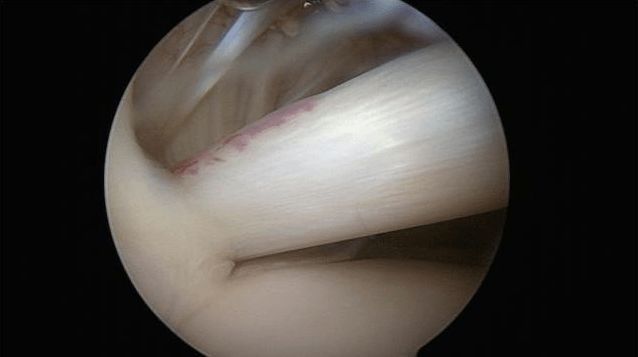

An arthral scan is recommended to locate the lesion, although only 45% of cases are detected. Only exploratory arthroscopy truly allows for a joint examination.

The surgery is performed arthroscopically and can be done on an outpatient basis.